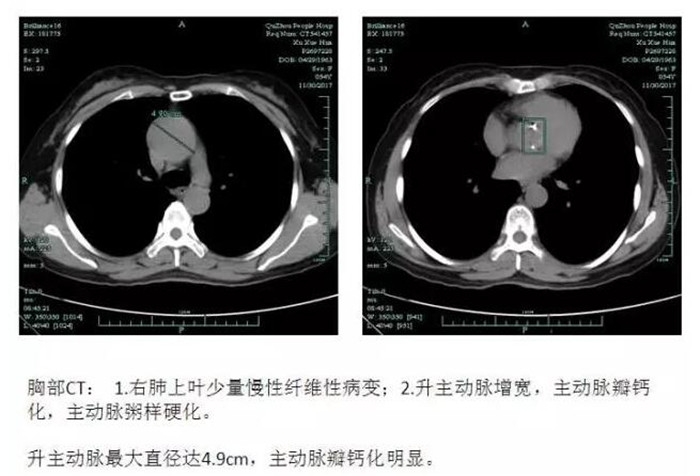

??? 54歲的徐阿姨,3年前開(kāi)始出現(xiàn)胸悶、氣喘癥狀,一直沒(méi)有引起重視。近半年來(lái),徐阿姨勞動(dòng)時(shí)心慌、氣喘等癥狀較之前明顯加重,休息后不能緩解,入住我院心胸外科。檢查后發(fā)現(xiàn)主動(dòng)脈根部?jī)H2.2cm,主動(dòng)脈瓣鈣化明顯,呈重度狹窄,主動(dòng)脈瓣二葉瓣畸形,升主動(dòng)脈瘤樣擴(kuò)張,最粗的地方直徑超過(guò)4.9cm。若不及時(shí)手術(shù)治療,隨著病情發(fā)展,會(huì)出現(xiàn)心律失常、血栓栓塞,將影響患者的正常生活,嚴(yán)重時(shí)還會(huì)造成心力衰竭,危及生命。